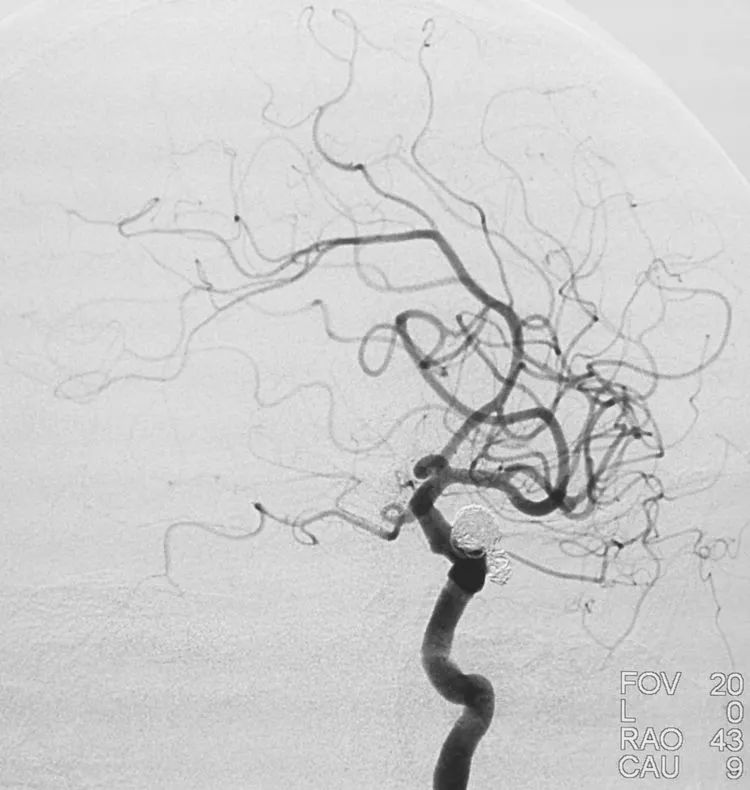

术后右颈内动脉工作位和三维旋转造影显示动脉瘤完全栓塞,前交通动脉保留:

术后左颈内动脉工作位造影显示动脉瘤完全栓塞,后交通动脉壶腹保留:

术后左颈内动脉工作位造影显示动脉瘤完全栓塞: